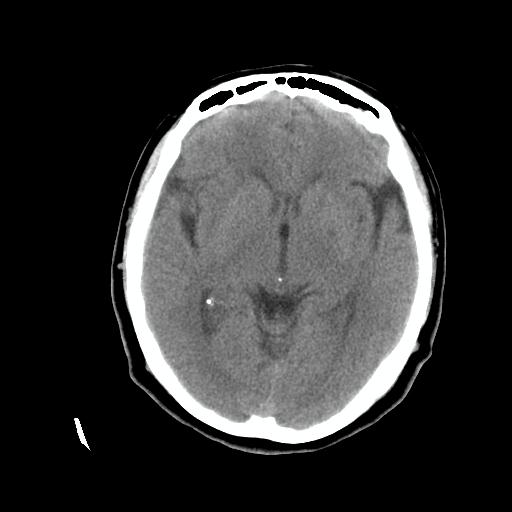

标题: CT24768:双侧脑室内囊性病变,主各位站友会诊。 [打印本页]

标题: CT24768:双侧脑室内囊性病变,主各位站友会诊。

患者女,62岁,临床提供头痛、头晕数月,无恶心及呕吐,近日加重。请各位站友看看,能否定为双侧脑室脉络丛囊肿,如果不能,应考虑什么?谢谢!

脉络丛囊肿属神经上皮性囊肿.好发于双侧脉络膜球,通常于影像检查或活检时偶然发现.患者无症状,病灶较小,双侧对称性,脑室膨胀轻.多数病灶在信号上与室管膜囊肿有所不同.在dwi上呈部分高信号,t2 flair上呈不均匀高信号.增强后呈结节状或环形增强

脉络丛囊肿属神经上皮性囊肿.好发于双侧脉络膜球,通常于影像检查或活检时偶然发现.患者无症状,病灶较小,双侧对称性,脑室膨胀轻.多数病灶在信号上与室管膜囊肿有所不同.在dwi上呈部分高信号,t2 flair上呈不均匀高信号.增强后呈结节状或环形增强!支持!